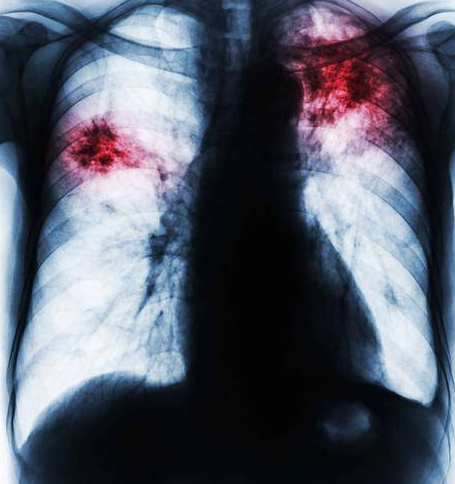

随着CT在体检中应用的越来越广泛,早期肺癌的检出率越来越高,而肺癌的早期形态大多表现为肺部小结节,这给很多肺上查出是结节的人带来了不小的困扰,尤其是医生阅片后怀疑小结节是恶性时,更加担心,每天茶饭不思,夜不能寐。那么肺结节一定就是肺癌吗?

肺部结节是指单发、边界清楚、直径小于或等于3cm、周围被含气肺组织包绕的结节。直径超过3cm属于肺肿块的范围。肺结节和肺肿块都有良性、恶性之分。一般来讲,孤立性肺结节恶性肿瘤的概率约20%-40%,恶性概率随年龄增高而明显增高。但如果肺结节是恶性肿瘤,早期确诊肺结节的性质,早期手术切除可以达到临床完全治愈,跟正常人一样,长期生存。